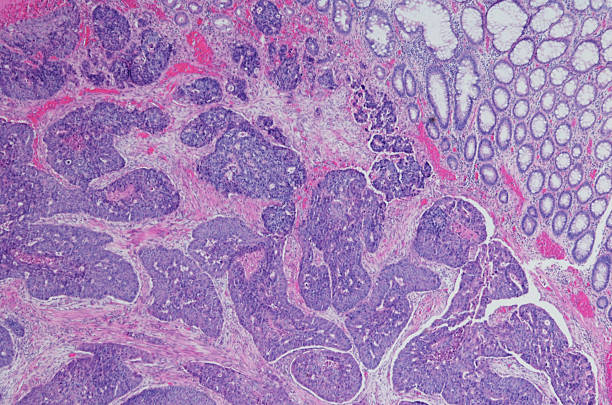

직장암의 초기 증상 중 하나로 장내 궤양 증상이 나타날 수 있습니다. 이는 직장암이 발생하면 종종 식도나 위처럼 소화기관의 다른 부분에서도 나타나는 것과 같은 원리로 발생합니다. 직장암이 진행되면 암세포가 장벽을 침범하여 장내 궤양을 일으키기 때문입니다. 장내 궤양은 대장 내부에서 발생하며, 복부팽만감과 함께 복통 및 가스 발생, 설사, 변색된 대변 등의 증상을 유발할 수 있습니다.